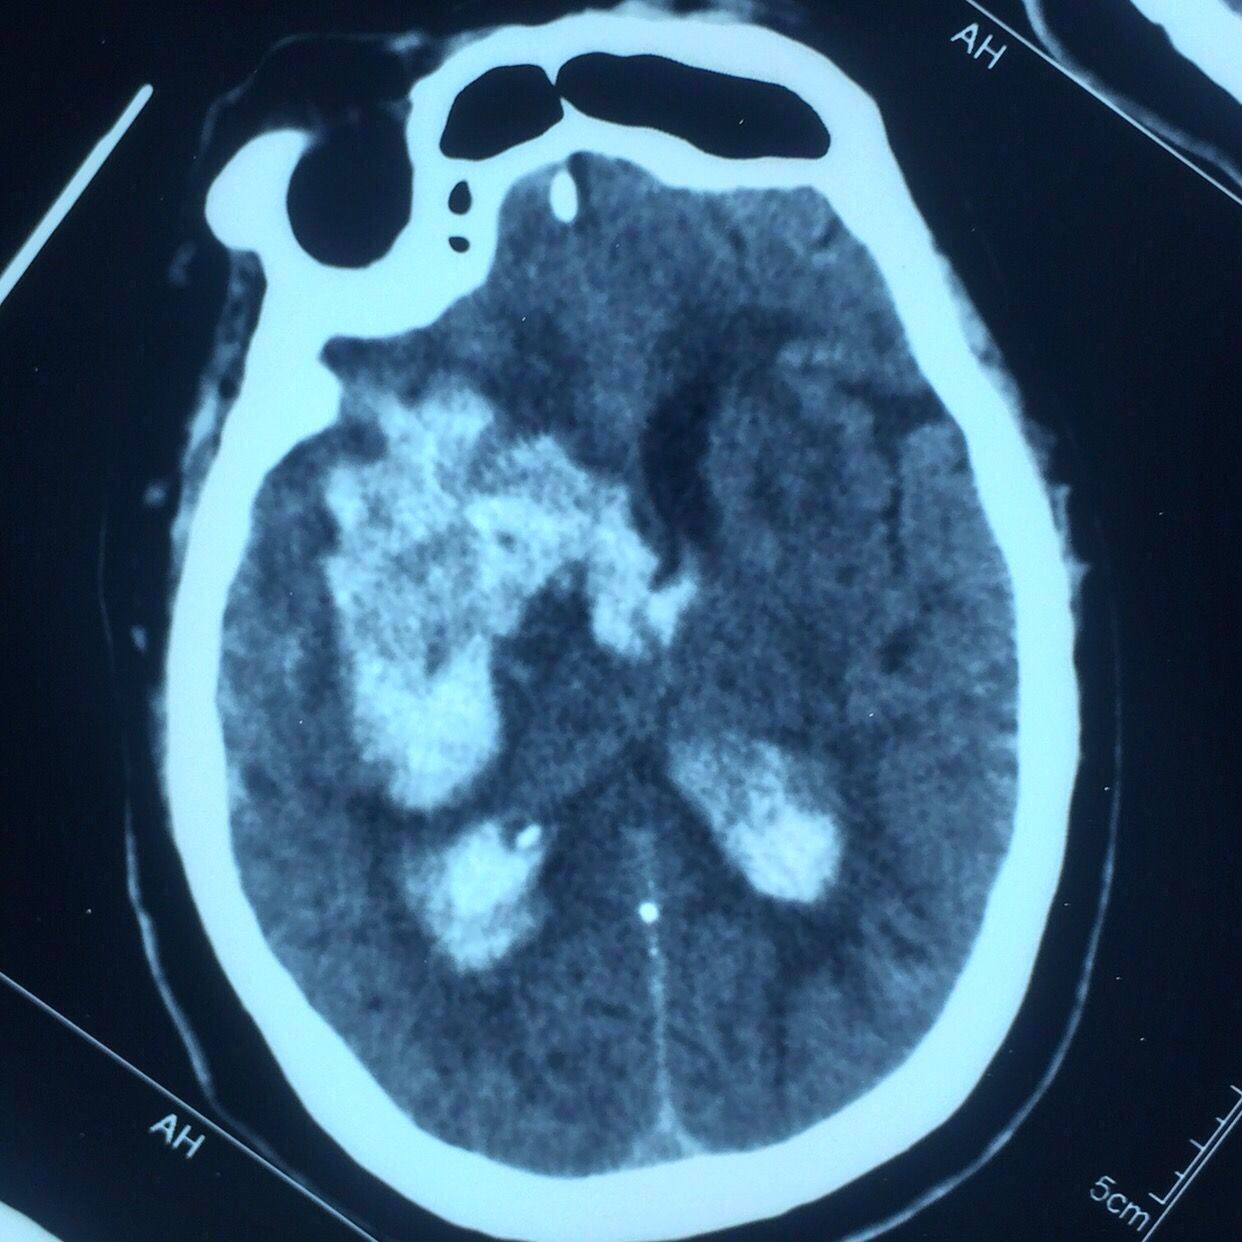

CT片见上图:

右侧基底节出血破入脑室脑积水